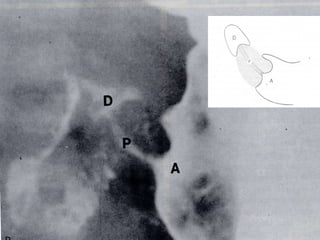

ESTENOSIS HIPERTROFICA DEL PILORO US DE ABDOMEN

ESTENOSIS HIPERTROFICA DELPILORO US DE ABDOMEN

ESTENOSIS HIPERTROFICA DELPILORO SERIE ESOFAGOGASTRODUODENAL